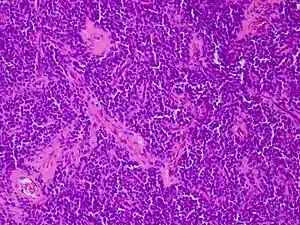

Micrograph of an H&E stained section of a peripheral PNET.